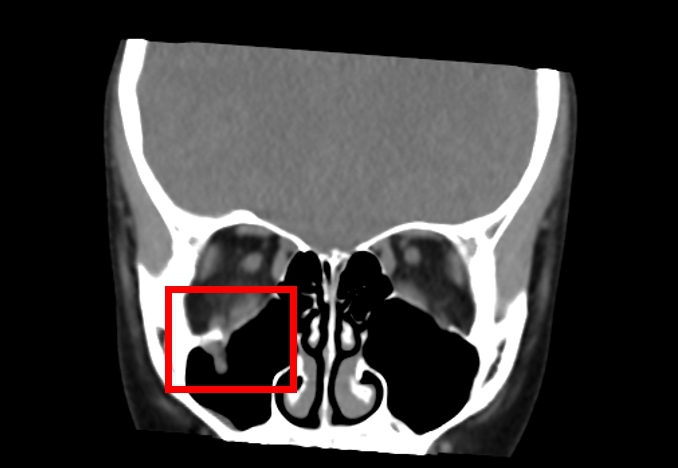

經評估後,中山醫學大學附設醫院口腔顎面外科醫療團隊邱昱瑋主治醫師、張芳語主治醫師及洪珮瑄主治醫師,立即制定手術方案,運用創新電腦數位模擬技術,術中搭配內視鏡與精密導航系統,精準定位眼底嵌頓肌肉的位置,成功將被夾住的眼底肌肉復位。術後,患者複視症狀消失,眼球活動恢復正常,並未留下相關併發症,順利重拾日常生活與學習品質。

中山附醫口腔顎面外科邱昱瑋主治醫師指出,眼窩骨折常見於眼眶底部,多因直徑大於眼球的鈍器撞擊,例如棒球、拳頭或意外碰撞,造成較薄的眶底骨因力量傳導而破裂。兒童的骨頭相對柔軟,更容易發生所謂「線性爆裂性骨折」,這種骨折機制如同門片回彈復位,容易將眼眶內的肌肉或其他軟組織嵌頓在骨折縫隙中,導致複視及眼球運動受限。值得注意的是,兒童眼窩骨折往往不伴明顯瘀青或紅腫,家長容易掉以輕心,邱昱瑋醫師也提醒,若眼底肌肉因缺血受損而無法及時復位,可能造成永久性功能障礙,理想治療黃金時間僅有24至48小時,超過此期限後併發症風險將大幅提升。

中山附醫口腔顎面外科張芳語主治醫師補充,重建受損眼眶骨在臨床上挑戰重重,包括手術視野狹小、骨頭型態複雜、手術精準度要求高,以及術後疤痕與外觀重建的考量,透過精準的數位導航技術,醫師團隊能克服這些困難,幫助患者安全恢復功能與外觀,重拾自信與生活品質。洪珮瑄醫師則強調,對於兒童患者而言,手術精準度與微創性格外重要,不僅要恢復功能,更要兼顧未來面容發育的完整性;該起案例不僅展現數位導航手術在顏面骨折治療上的價值,也提醒家長與學校,即便外觀無傷痕,一旦出現眼球運動受限或複視症狀,應立即就醫,避免錯過黃金治療期。